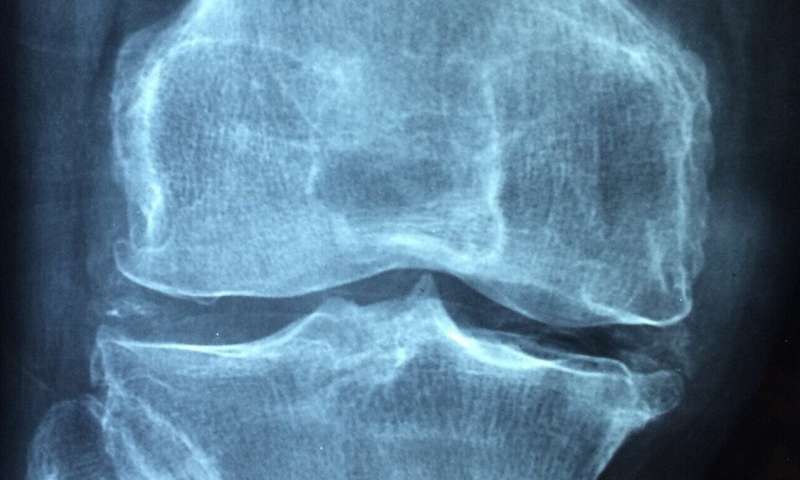

La investigación encontró que en los

perros que habían sufrido un desgarro de ligamentos en la rodilla, la lubricina

aumentaba dentro de la articulación, lo contrario de las suposiciones

convencionales en medicina, donde se creía que disminuía en las enfermedades de

las articulaciones.

Esto indica que un aumento de

lubricina en realidad podría ser un biomarcador para predecir la osteoartritis en

el futuro. También apreciaron un aumento de lubricina en perros meses o años

después de que se lesionaran el ligamento cruzado anterior, lo que sugiere que

la lubricina podría ser un indicador de inestabilidad articular en curso. El

aumento de lubricina podría ser una señal para que los médicos intervengan o

prueben un enfoque de tratamiento diferente.

No existe un consenso unificado sobre cómo se altera la lubricina en otras especies veterinarias domésticas y en las lesiones articulares humanas, lo que demuestra la necesidad de más estudios. En el ámbito veterinario, el equipo planea realizar un estudio longitudinal de seguimiento en perros, examinando múltiples puntos de tiempo en el proceso de lesión, tratamiento y recuperación de un paciente. También esperan establecer conexiones similares en el ligamento cruzado anterior humano y otras lesiones ortopédicas.